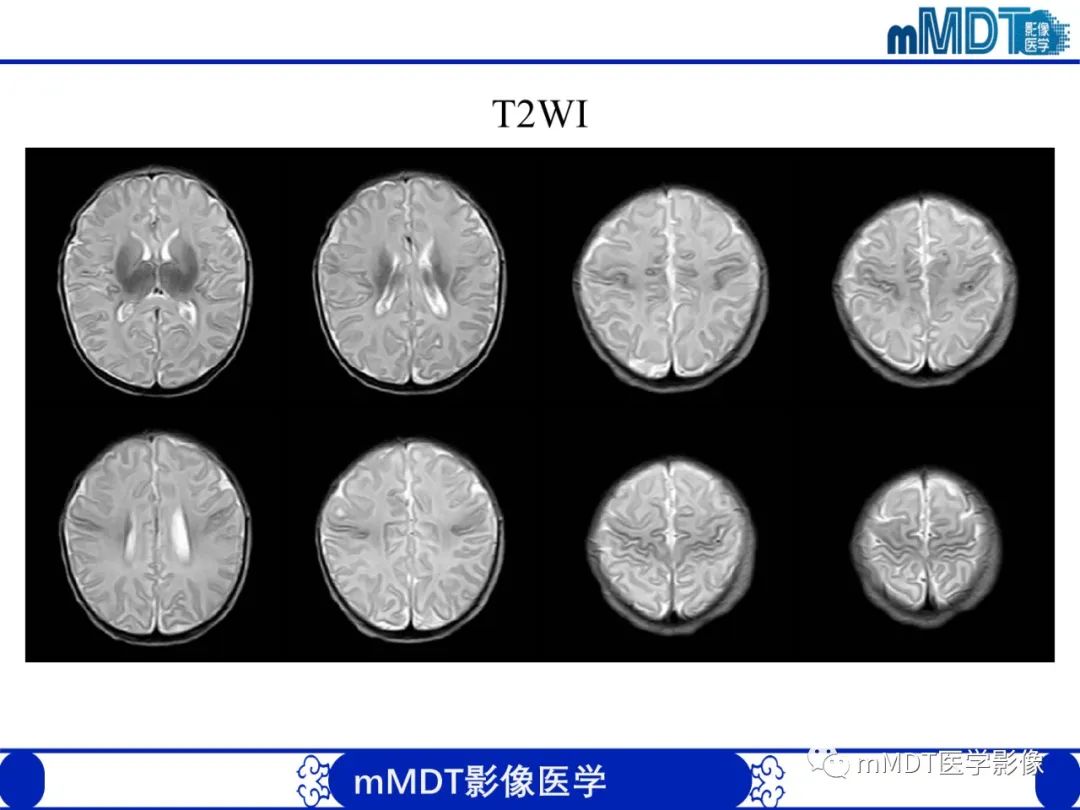

早产儿HIE

Ø脑损伤的部位—-脑室周围为主ØØ脑损伤类型、发病机制:

l脑室旁白质软化(periventricularleukomalacia,PVL),血管的终末段(胎龄越小,髓质穿通动脉发育越差,分支少),缺血易发生白质的坏死。